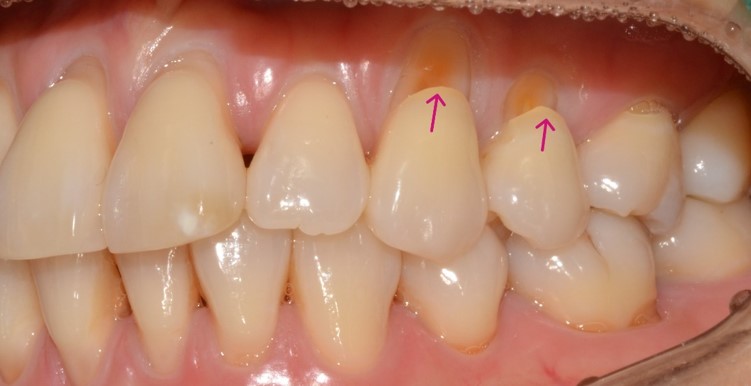

치료 전 사진 부터 함께 보도록 하겠습니다. 위에서 말씀 드린 것과 같이 이가 시린 것으로 인해 내원을 해주신 환자분이셨는데요. 검진을 해보니 잇몸쪽에 치아 뿌리가 노출되면서 마모가 심하게 된 상태라는 것을 확인할 수 있었습니다. 이러한 증상은 '치경부 마모'라고 말씀드릴 수 있는데요. 교합력에 의해서 치아의 가장 얇은 부위가 마모되어 안에 있는 치아 뿌리의 안쪽 신경이 외부와 가까워져서 예민하게 느껴지는 현상입니다. 이로 인해서 치아 시림을 더 잘 느끼고 계셨던 것이죠!

치료 전 - 2025.01.08